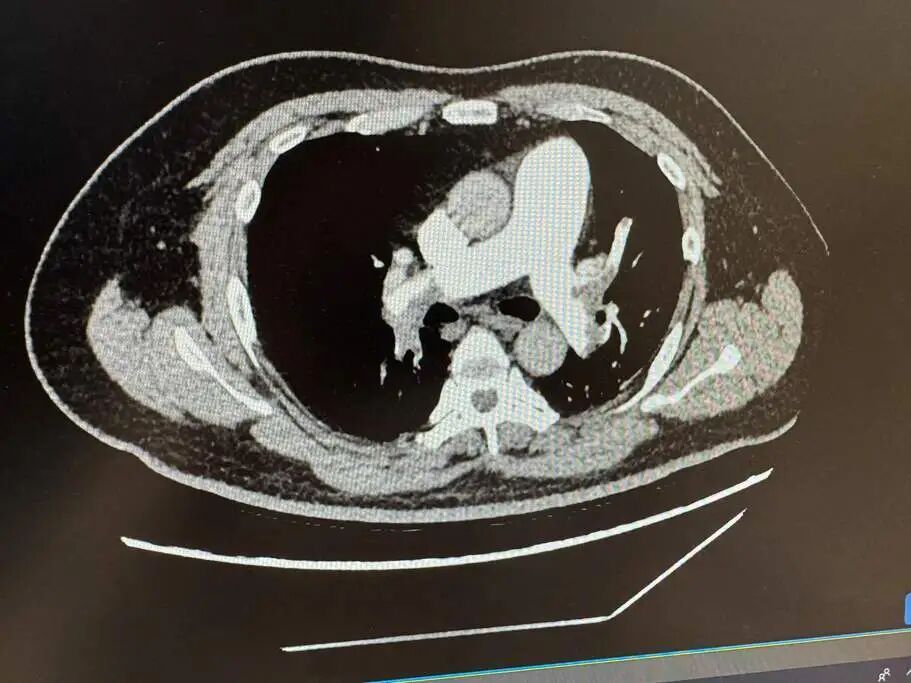

“我们紧急给他做了肺动脉CTA检查,结果显示,他的肺动脉主干有明显血栓堵塞,属于大面积肺栓塞。”李燕说,进一步检查发现,张志的血栓指标D-二聚体指标远超正常上限,是普通人20倍。“这种情况非常危急,血栓堵塞了肺部供血的‘主干道’,再晚30分钟送医,就可能会要命,引发呼吸衰竭、休克,甚至猝死。”

张志肺部出现大面积肺栓塞。

三天后,复查肺动脉CTA显示,堵塞的血栓明显溶解,张志的呼吸、血压恢复正常,不再有晕厥、胸闷的症状。